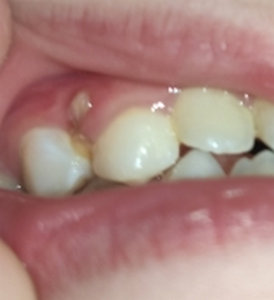

Мне 26 лет, молочные зубы менялись поздно. По личным причинам, когда стал резаться коренной зуб (клык), я не стала вырывать молочный, который был крепким и здоровым. Так на протяжении нескольких лет (очень медленно) прорезался коренной клык и наконец вырос, но на нёбе. Так я ходила с двумя зубками. Никаких неудобств не ощущала. Совсем недавно молочный зуб резко (в течение трёх дней) потемнел.

Помогите, пожалуйста,что нужно делать, удалять оба зуба и ставить мартини? Или после удаления молочного одевать брекеты и ждать пока сдвинется коренной клык?